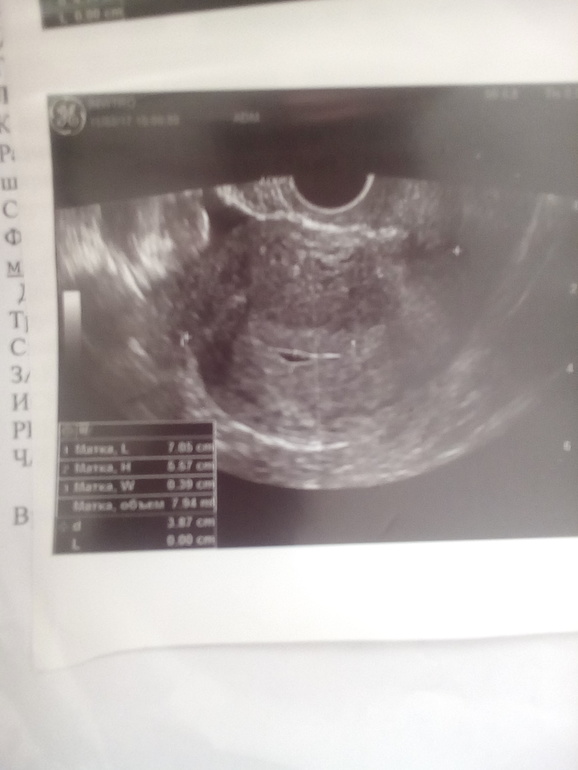

Это ещё не плодное яйцо, это жидкость в полости матки. Такая картина может быть и при маточной и при внематочной беременности. Сдайте кровь на хгч, если меньше 1000, то и не должно ещё быть плодного яйца.

Ну как... Не кругляш на УЗИ, а полоса. И эмбриона не видать( Неизвестность гложит(

Неееет, совсем не рано это точно! Уже точечка в кругляше как минимум. Ну допущу что матка старая, нет ещё точечки, но почему полоса вместо обычного круга... Даже интернет ничего подобного не выдает

У меня вечно лаборатории ошибаются, я верю только тому, что вижу на экране. По идее должен быть на узи хотя бы круг чёрный с белой окантовкой, а тут полоса!. Я с таким не сталкивалась, гугл что то ничего похожего не выдаёт. Ни в поисковике месячных, ни в беременности

Мой узист уволился( она насчитала 4 недели, но с учётом овуляции+ прикрепление 2,5 эмбриональных должно быть, по моим подсчетам, те на УЗИ уже видно